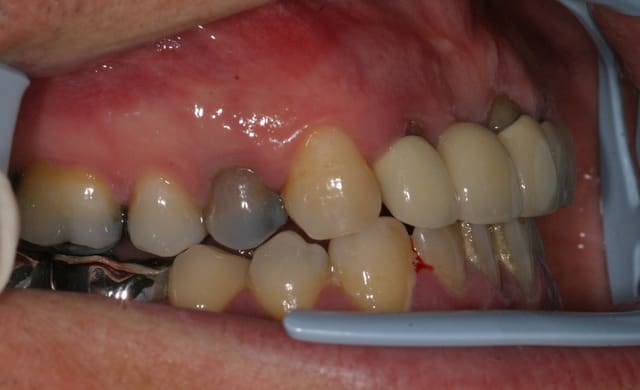

Je stressais pas mal sur ce cas quant à la réussite du conj. enf. avec lamb. tracté coronairement. Mais le résultat est acceptable je pense, car on partait de loin.

Bravo, suis incapable de faire autant. Juste une interrogation, les limites des preparations sont juxta gingivales?

Si oui, n est il pas souhaitable de les remonter en supra pour soulager le parodonte et eviter une nouvelle recession?

Juxta en vest, supra en linguale, et infra en proximal.

Dans le cas d'un biotype fin vest peut-être , quoi que en pratique la limite supra/juxta est parfois minime. Ici le biotype est devenu épais, donc c'est juxta avec CCC ce qui est bien plus agréable pour le parodonte.

Il faut aussi voir ici l'anatomie des dents qui rendait les préparations délicates au niveau périphérique.